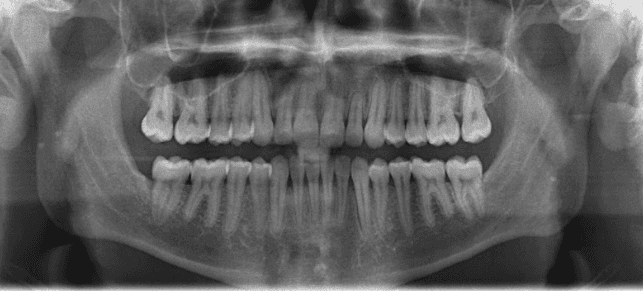

Diagnosis: Class III malocclusion, edge-to-edge anterior relationship, lower anterior crowding

X-RAYS